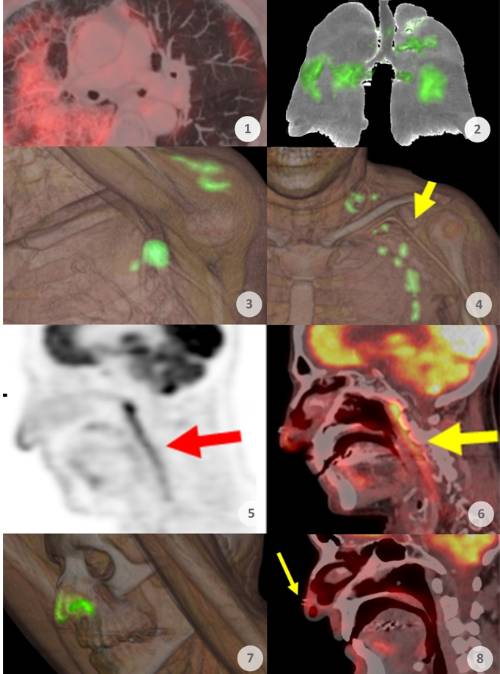

Desde el inicio de la pandemia del COVID-19 el Servicio de Medicina Nuclear del Hospital Universitario Quirónsalud Madrid ha estado tratando a sus pacientes sometiéndoles a pruebas de PET-CT. Sus imágenes muestran cómo ha sido la evolución de la pandemia durante estos dos últimos años. "Durante la primera ola, a partir de marzo de 2020, era muy frecuente observar afectaciones pulmonares (imágenes 1 y 2). Llegó a apreciarse en el 4 por ciento de todos los pacientes a los que sometemos a pruebas PET", explica el Dr. Antonio Maldonado

, jefe del Servicio de Medicina Nuclear de Quirónsalud Madrid, que afirma que el COVID-19 no deja de ser una vasculitis sistémica que afectaba a vasos de diferentes niveles. "Después, con el inicio de la vacunación desde principios de 2021, comenzamos a observar captaciones locales en la zona del hombro con extensión ganglionar, e incluso en el bazo debido a la vacunación (imágenes 3 y 4). Observamos que en nuestra serie de pacientes la vacuna de Moderna fue la que más reacción producía, que generalmente provocaba también captación en los ganglios adyacentes a la zona de vacunación".

En cambio, con la llegada y generalización de la variante ómicron a finales de 2021 se ha observado un cambio de patrón: "Ya no observamos afectaciones pulmonares como en la primera ola, sino que se aprecian con frecuencia captaciones en las mucosas oro y nasofaríngeas (imágenes 5 y 6). Este nuevo patrón lo observamos desde diciembre de 2021".

El último hallazgo que ha alimentado la curiosidad del equipo de Medicina Nuclear son las captaciones en la punta de la nariz de muchos enfermos (imágenes 7 y 8): "Los denominados hallazgos de superficie de anclaje nasal. Creemos que muestra actividad producida por el ajuste de la mascarilla con la mano, pero aún no estamos seguros porque no la habíamos visto con tanta frecuencia hace unos meses cuando también se utilizaba la mascarilla. Debemos seguir estudiando".